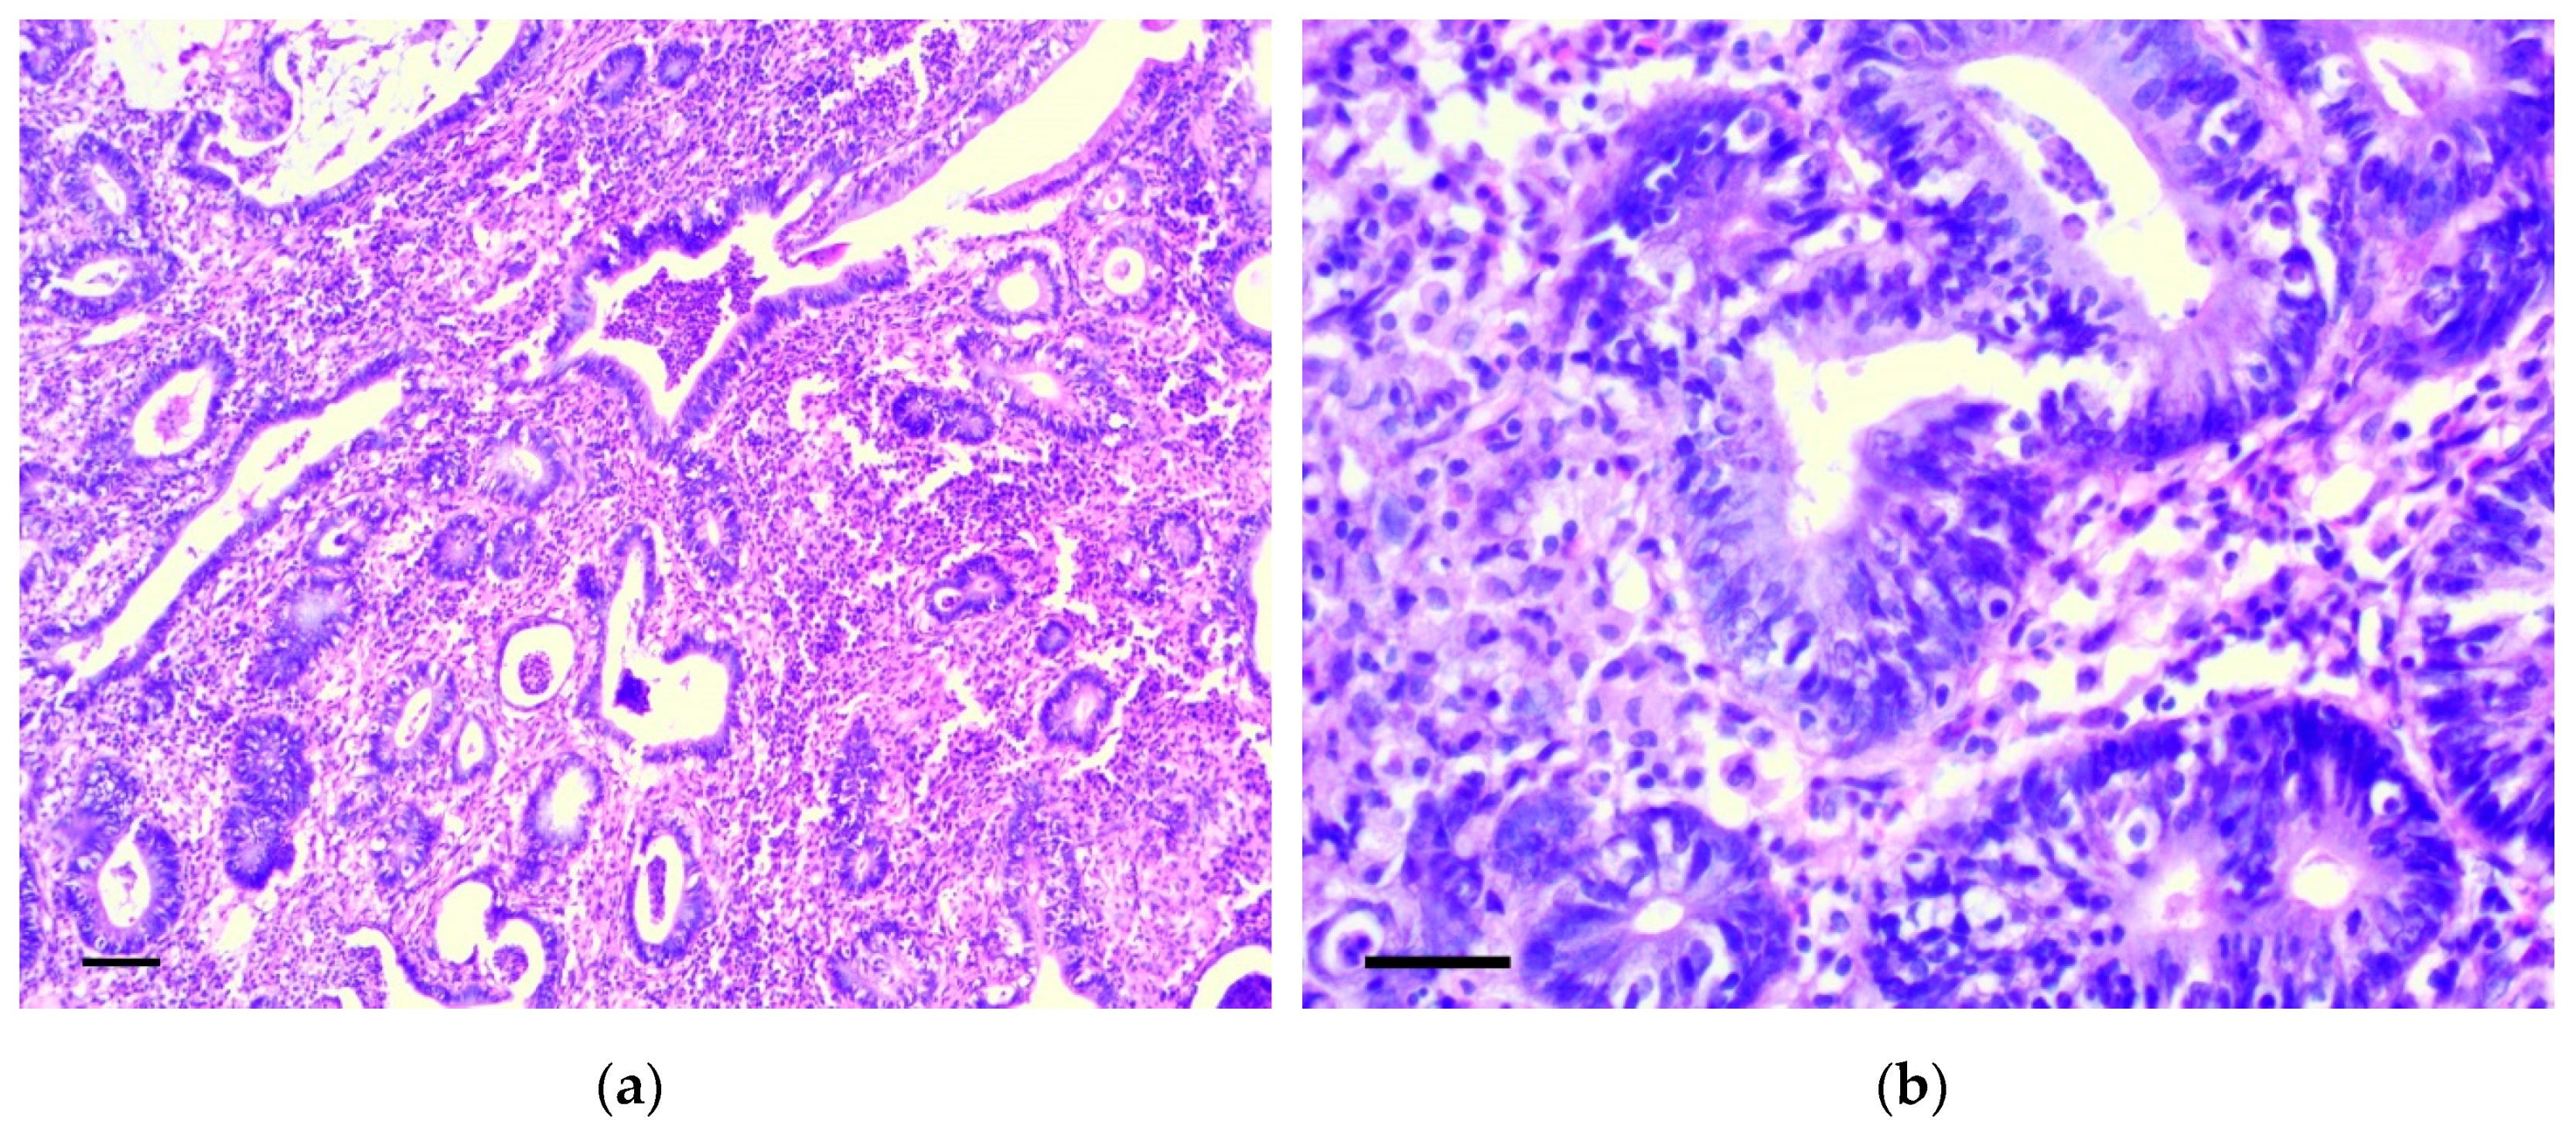

3.1. Pathology of the Gastric Tumor